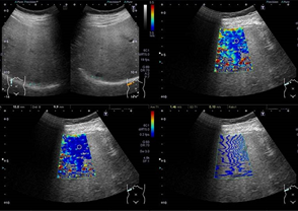

検査用のゼリーを塗りプローブ(探触子)を当てて観察します。

高周波数の音波を腹部にあて、臓器の状態を調べる検査です。心臓や肝臓、胆嚢、膵臓、腎臓、脾臓、乳腺の様子を観察することができます。検査は、X線検査でないので、「被ばく」もなく安全な検査です。

造影検査等の最新技術を用いた精密検査も積極的に行っています。